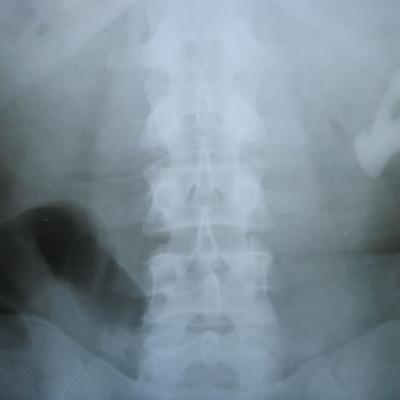

Здравствуйте! Подскажите, пожалуйста, до каких размеров камня в почке возможно его дробление. У меня был в 1994 г. удален коралловидный камень из правой почки ок. 4 см. Потом, естественно, опять стал расти. 3 раза было отхождение камней, самый большой из которых 2.5 см(!)х0,8 (Вы не верите, а он передо мной). Сейчас, по заключению УЗИ, в ср. сегм. 1,2 см, в нижн. 0, 9 и множеств. 0,5-1.2 см. Второе независимое УЗИ предполагает, что это фрагменты коралла. Судя по рентгеновскому снимку,  уролог  предполагает, что 3 камня, один из которых коралл до 5 см. и предлагает  удаление почки. Я считаю, что это крайняя мера и пытаюсь найти решение. Если это возможно в России, то как получить  квоту, читала на вашем сайте. Да, у меня неполное удвоение правой почки. Спасибо за ответ и за сайт, который действительно помогает многим. С ув. Ирина

1. В Вашем случае можно попытаться выполнить перкутанную нефролитотомию (новая малоинвазивная методика - удаление камня через прокол в поясничной области) или открытую операцию по удалению коралловидного камня. Но, конечно, гарантий, что почку удастся сохранить, Вам никто не даст. ДЛТ камней выполняется до размеров камня 2 см. Это максимум.